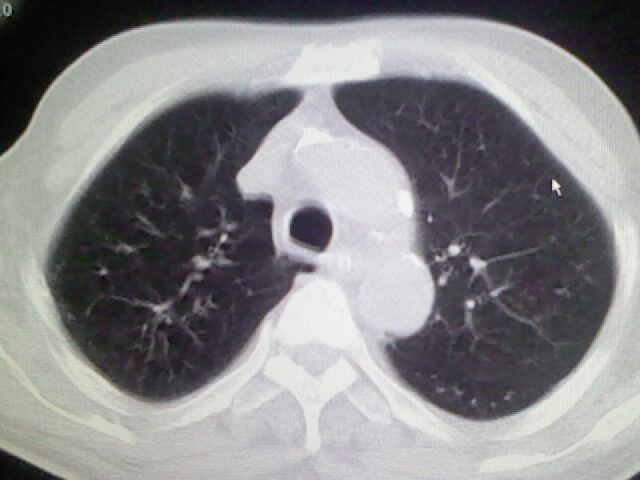

右肺病灶考虑炎症性。

右肺病灶考虑炎症性

考虑右肺及左肺下叶炎症。

右肺及左肺下叶炎症。

考虑右肺及左肺下叶慢性炎症。

右肺上叶前段病呈楔形,其尖端指向肺门,考虑肺动脉栓塞可能性大.